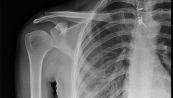

Chụp X-quang là chụp ảnh phóng xạ thường được thực hiện nhất. Chụp X-quang thường trong thủ tục đầu tiên mà sẽ trải qua nếu bác sĩ nghi ngờ có bệnh tim hoặc phổi. Để hiểu rõ hơn về phương pháp này, mời các bạn cùng tham khảo bài viết dưới đây.